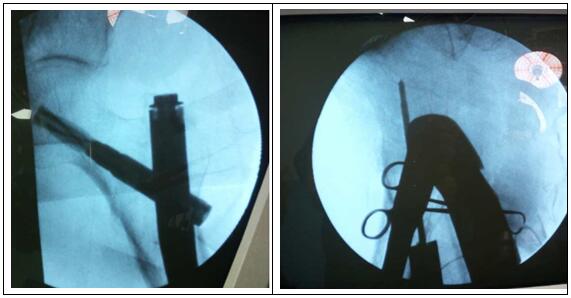

圖片二:(術(shù)中照片)

科主任楊志奎帶領(lǐng)曹熙、田濤、安蒙蒙、張凱迪醫(yī)師,經(jīng)充分討論,考慮到患者高齡,合并高血壓、冠心病等多種基礎(chǔ)疾病。自身恢復(fù)能力不強(qiáng),身體機(jī)能較差,已承擔(dān)不起傳統(tǒng)開放性手術(shù)所帶來的創(chuàng)傷。為改善患者生活質(zhì)量,再次站立起來,根據(jù)骨折類型,為老人選擇行閉合復(fù)位股骨近端骨折PFNA髓內(nèi)內(nèi)固定方式。手術(shù)時長約35分鐘,術(shù)中透視骨折復(fù)位滿意,內(nèi)固定裝置位置適當(dāng)。術(shù)后第1天,即指導(dǎo)患者行左髖、膝關(guān)節(jié)屈伸活動鍛煉,術(shù)后第2天可坐起。